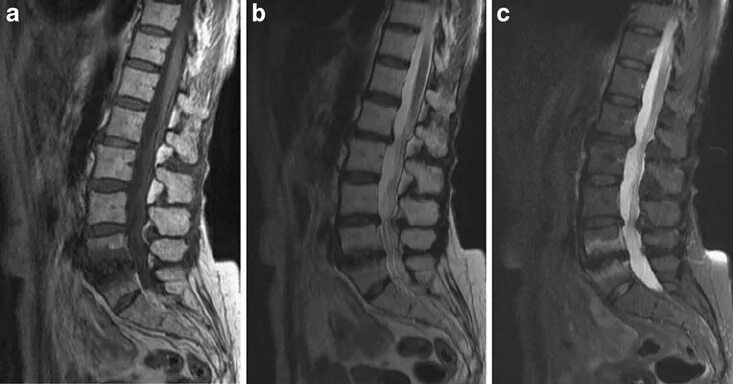

Изменения modic 2